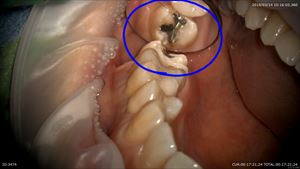

さて本日の歯の金属を外し

感染を取り